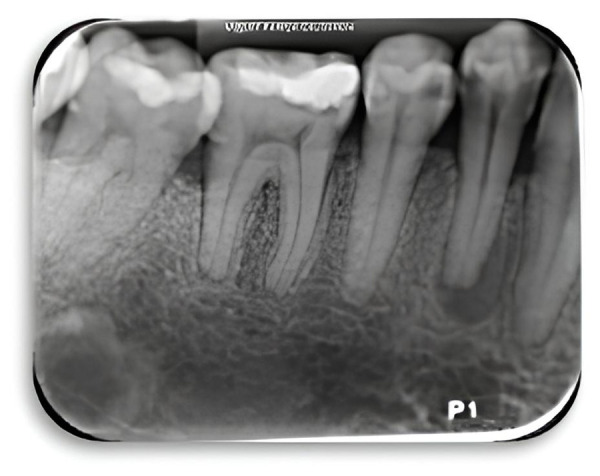

牙髓环境为微生物的生长提供了最佳条件,这些微生物会将副产品释放到牙齿根尖周围区域并引起炎性病变。使用刺激性溶液进行化学消毒在临床上发挥着重要作用,因为它们能够清除受污染的有机和无机组织中的废物,产生残留的抗菌效果。本研究的目的是显示 2.5% 和 5.25% 次氯酸钠作为冲洗剂在临床治疗一颗根尖吸收牙的慢性根尖周围脓肿中的有效性。最初使用的是 2.5% 的次氯酸钠,但由于 3 天后脓肿愈合反应并不理想,因此决定使用浓度为 5.25% 的次氯酸钠,以达到更好的杀菌效果。5 天后,瘘管愈合,牙髓治疗继续进行。本病例报告的视角之一是进一步研究抗生素治疗与良好冲洗方案的结合使用。

The endodontic environment has optimal conditions for the growth of microorganisms that can release by-products into the periapical region of the tooth and cause inflammatory lesions. Chemical disinfection using irritants solutions plays an clinical important role, as they are able to remove waste from contaminated organic and inorganic tissues, generating a residual antibacterial effect. The purpose of this study was to show the effectiveness of 2.5% and 5.25% sodium hypochlorite as an irrigating agent for the clinical management of a chronic periapical abscess in a tooth with apical resorption. Initially, 2.5% sodium hypochlorite was used, however, as it did not have an optimal abscess healing response after 3 days, it was decided to use a concentration of 5.25% to achieve a better bactericidal effect. After 5 days, the fistula healed, and endodontic treatment continued. One of the perspectives of this case report is to investigate more about the use of antibiotic therapy in conjunction with a good irrigation protocol.